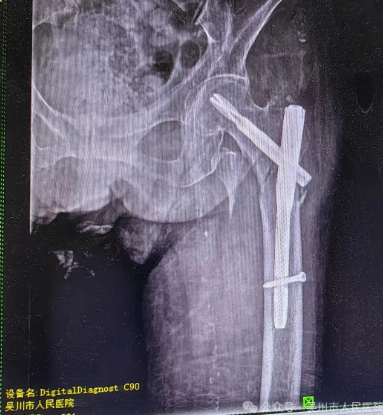

了解患者的情况后,我院骨外科三区主任、主任医师曾维,主治医师宁健文和护士长刘春莲带领医护团队第一时间为李某完善相关检查,明确诊断为 “左股骨粗隆间骨折”,并结合患者的年龄、身体状况制定了个性化的治疗方案。11月21日,该科手术团队凭借精湛的医术,顺利为李某实施 “左股骨粗隆间骨折切开复位髓内针内固定术”。在术后恢复期间,医护团队更是给予了李某全方位的细致照护,让远在他乡的李某感受到我院医护人员如同家人般的关怀与温暖。

术前/术后对比